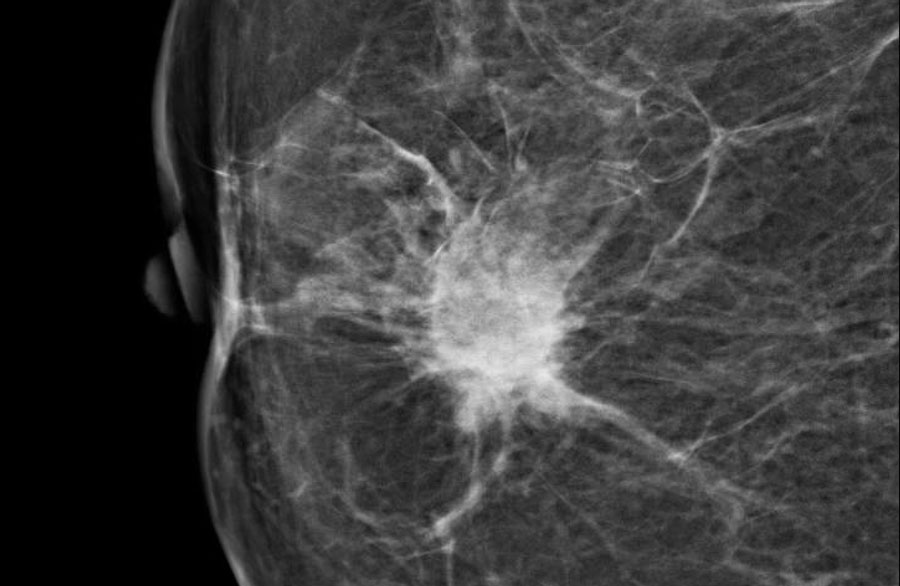

Феномен гипердиагностики в маммографии: примеры и иллюстрации

Раздел: Образы вокруг